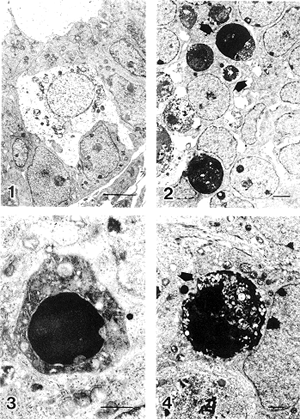

在出生当日,可见个别呈坏死特征的变性生殖细胞,核质溶解,但无染色质聚集;核周隙扩大,线粒体和内质网等细胞器肿胀,有空泡形成。细胞膜有突起、出泡现象(图1)。生后1d,死亡细胞罕见。生后4d开始见到典型凋亡特征的生殖细胞,并于生后10~13 d达到高峰(图2),而后凋亡细胞逐渐减少。凋亡生殖细胞早期出现核染色质聚集(图3),细胞器如线粒体和内质网无明显变性;中期除核染色质积聚外,细胞器也肿胀变性(图2);晚期细胞核碎裂,细胞器溶解,细胞常碎裂为几部分,成为凋亡小体(图2,4)。

图1 生后0d,生殖细胞的坏死图像 标尺示2μm

图2 生后10d,可见较多凋亡的生殖细胞,箭头示凋亡小体 标尺示2μm

图3 生后10d,生殖细胞凋亡的早期图像 标记示1μm

图4 生后18d,生殖细胞凋亡的晚期图像 箭头示凋亡小体 标记示1μm

Fig.1 0 day after birth, a necrotic figure of a germ cell. Bar=2μm

Fig.2 10 day after birth, many apoptotic figures of germ cells could be found. Arrows point

to apoptotic bodies. Bar=2μm

Fig.3 10 day after birth, an apoptotic figure of germ cell at early stage. Bar=1μm

Fig.4 18 day after birth, two apoptotic figures at late stage. Arrow points to a apoptotic body. Bar=1μm